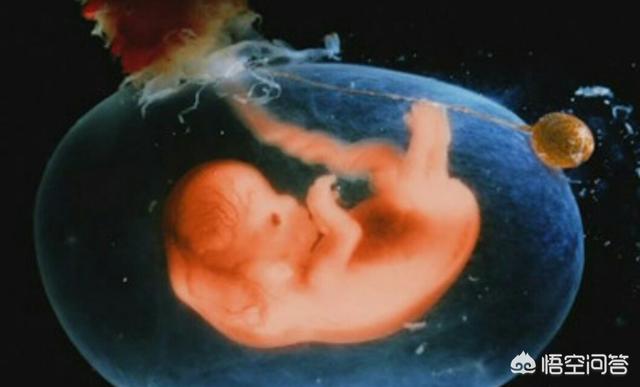

胎儿的脑袋和身体的比例降到了1:3,比以前更加协调,像个小人了。

20颗牙齿已经长在了牙床下面,胎儿的手指还有了指纹,胎儿的身上也盖上了一层细软的绒毛,毛绒绒地更加可爱了。

胰腺、肾脏、输尿管开始工作,脐带也开始进行营养与代谢废物地交换了。